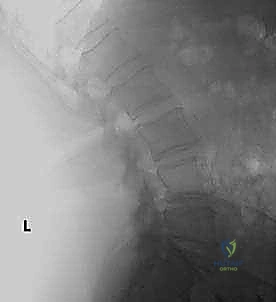

* الأشعة السينية (X-rays): خاصة الصور الديناميكية (أثناء الانحناء للأمام والخلف) لتقييم درجة عدم الاستقرار الميكانيكي والانزلاق.

* التصوير المقطعي المحوسب (CT Scan): يوفر صوراً ثلاثية الأبعاد للعظام، وهو ضروري جداً للتخطيط الجراحي الدقيق وتحديد أحجام المسامير المناسبة لكل سويقة فقارية.